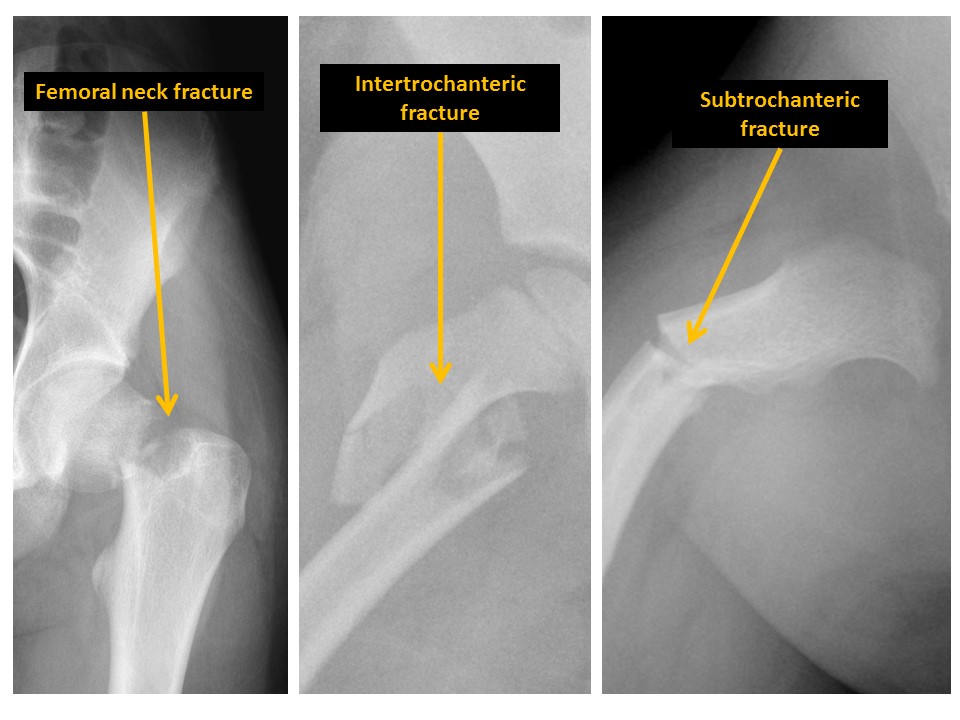

There are fractures of the femoral neck, intertrochanteric region, or subtrochanteric region. [Yes/No]